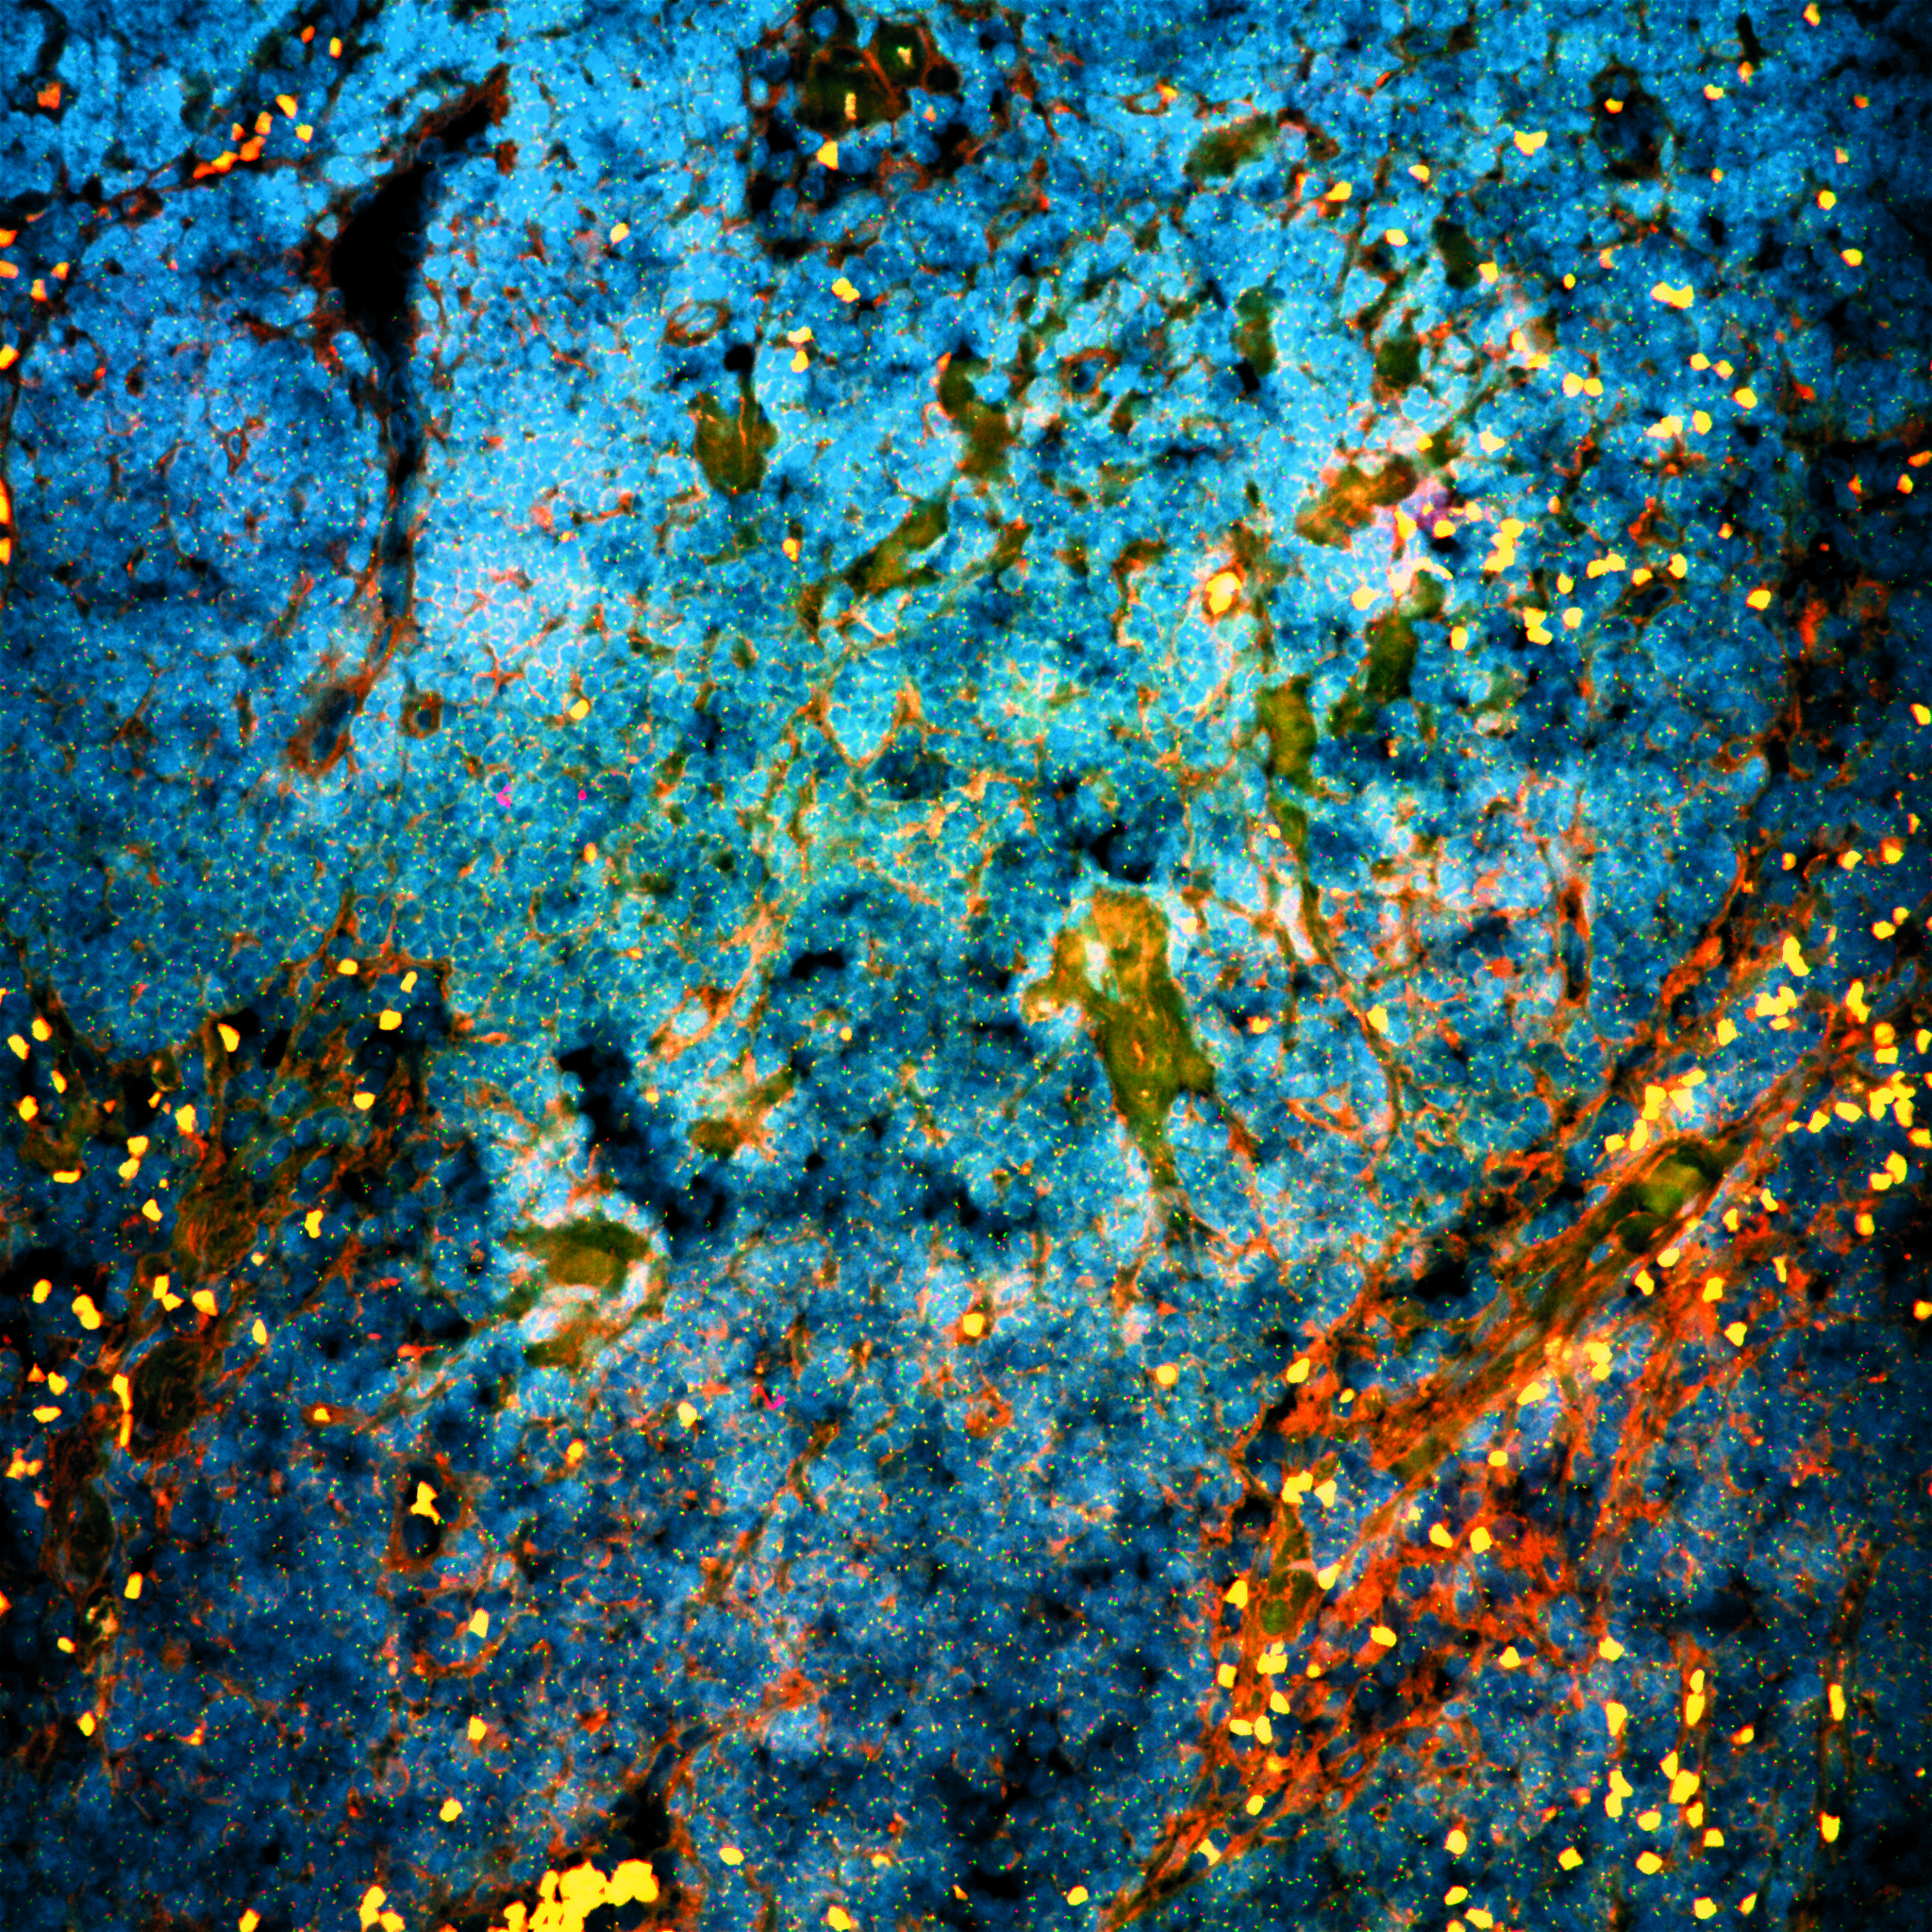

The study was based on tissue from 56 patients with high-risk prostate cancer, who had received three months of anti-hormonal therapy before their surgery. After those three months, their tissue was examined at the DNA level. 'We noticed that the genes keeping the tumor cells alive despite the treatment, were suddenly controlled by a protein that normally regulates the circadian clock,' says researcher Simon Linder, who will receive his PhD for his research in this study. This surprising discovery also creates new opportunities, because inhibition of this circadian protein was found to further increase sensitivity to anti-hormonal therapy in prostate tumor cells in the lab as well as in mice.